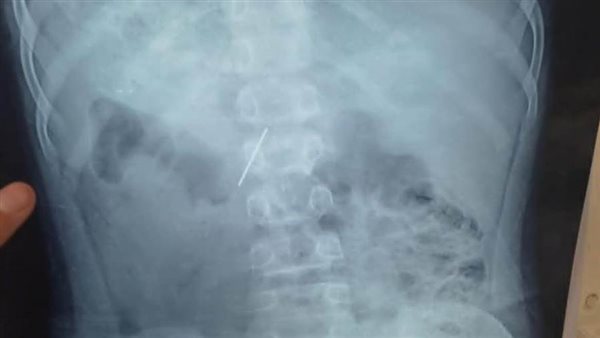

نجح قسم جراحة الأطفال بمستشفى الأطفال التخصصي ببنها، في استخراج مسمار دباسة كراسة اخترق جدار بطن طفل واستقر داخل التجويف البطني، بعد تدخّل جراحي متقدّم جمع بين المنظار الجراحي وجهاز السي أرم لتحديد الموقع بدقة متناهية.

قاد العملية فريق متميز بقيادة الدكتور محمد متولى رئيس قسم جراحة الأطفال، وبمشاركة د. وليد محمد استشاري جراحة الأطفال ود. محمود ممدوح نائب قسم جراحة الأطفال، تم توظيف المنظار الجراحي لتقليل آثار الجراحة والشفاء السريع، فيما لعب جهاز السي أرم دور الخريطة الحية لتحديد موقع المسمار بدقة مدهشة، ما حول العملية إلى مزيج من مهارة الجراح وذكاء الأجهزة.